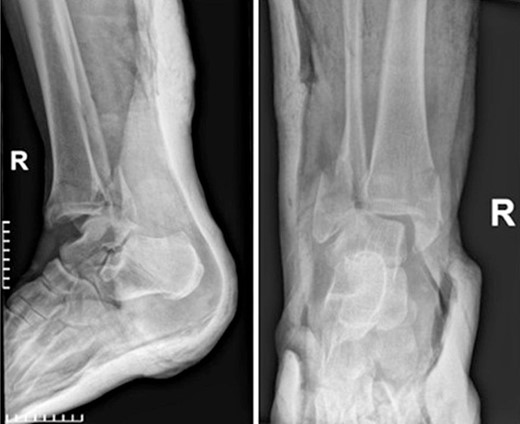

A surgical treatment was decided, consisting of ORIF of the fracture which was addressed within 48 hours of the admission to the hospital. Fracture reduction was achieved through a lateral and medial approach to the lateral and medial malleolar, respectively. A 3.5-mm neutralization plate with a lag screw was applied on the lateral malleolus combined with a 3.5-mm lag screw fixation of the medial malleolus and a 3.5-mm syndesmotic screw fixation (Fig. 2).

Postoperative anteroposterior and lateral X-ray of the ankle joint after ORIF of the fracture.